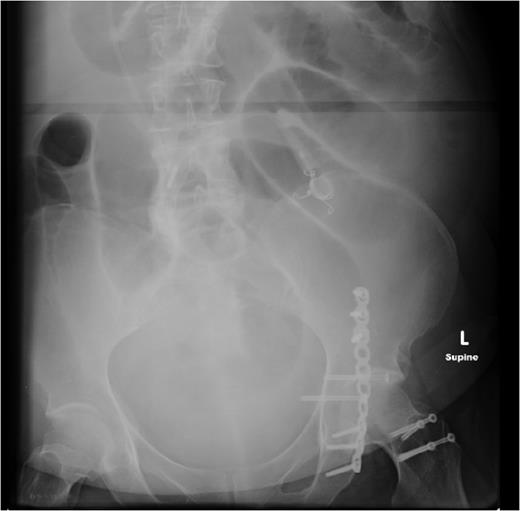

Two weeks later, she re-presented to the emergency department with a 24-hour history of severe central abdominal pain associated with vomiting and multiple episodes of loose stools. On examination, she was found to be hypotensive, tachycardic and peritonitic. The suspicion of an SBO was established by plain film radiograph appearances with multiple air fluid levels and distended bowel loops (Fig. 1). Computed tomography scan of the abdomen and pelvis showed the transitional zone to be in mid abdomen (Fig. 2). This was thought to be most likely secondary to adhesions. She proceeded on to have an emergency laparoscopy. Interestingly, the laparoscopy identified the transition point of the SBO to be an adhesion formed between the LAGB tube, the mid jejunum and the stomach forming a classic closed-loop obstruction (Fig. 3). The laparoscopic division of this adhesion was performed successfully. The rest of the small bowel was run along its entire length with no other transition point found. The adjustable gastric band was removed at the same time along with the associated port. Postoperatively, she had an uncomplicated recovery and was discharged on Day 4 post-admission without further sequelae.

SBO established on plain abdominal radiograph, with gastric band tubing and port also evident.